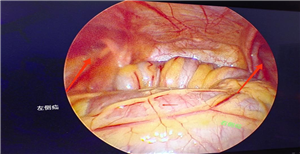

术前检查彩超及CT均提示左侧腹股沟斜疝,患者既往右侧腹股沟区也未发现可复性包块。术中发现左侧疝并网膜嵌顿,右侧腹壁下血管外侧缺损,诊断双侧腹股沟斜疝。遂行双侧疝囊高位结扎术,术后恢复良好出院。